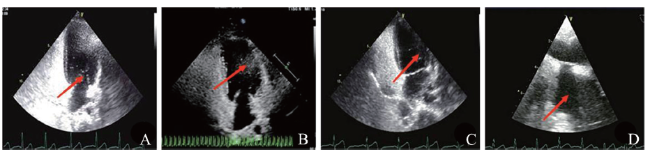

头痛、头晕是儿童和青少年常见的躯体症状之一,但其诊断无客观生物学指标,且儿童不能准确理解与描述头痛和头晕的性质,因此以头痛和(或)头晕为主诉的卵圆孔未闭(PFO)患儿易被误诊或漏诊。该文报道3例患儿,均以头痛和(或)头晕为主诉。例1经心脏彩色多普勒超声(彩超)、右心声学造影、经颅多普勒超声(TCD)发泡试验确诊为无先兆型偏头痛合并PFO,接受卵圆孔封堵术后恢复良好。例2经右心声学造影、经食管超声心动图确诊PFO,予口服硫酸氢氯吡格雷片治疗,出院后仍有头晕,无明显头痛,未规律用药。例3经右心声学造影及 TCD发泡试验诊断为PFO,予口服阿司匹林片治疗,规律用药,症状未再发。对于表现为头痛和(或)头晕的患儿,在排除常见病因后,行右心声学造影及TCD发泡试验有助于早期发现PFO及相关异常,值得临床推广应用。

Headache and dizziness are common physical symptoms in children and adolescents. However, no objective diagnostic biomarkers are available. Moreover, children fail to accurately understand and describe the nature of headache and dizziness. Therefore, it is likely to misdiagnose or miss the diagnosis of children with patent foramen ovale (PFO) presenting with headache and (or) dizziness as chief complaints. In this article, three children diagnosed with PFO developed headache and(or) dizziness as chief complaints. Case Ⅰ was diagnosed with migraine without aura complicated with PFO by heart color Doppler ultrasound (color ultrasound), right echocardiography and transcranial Doppler (TCD) bubble test, who was recovered well after undergoing PFO closure. Case Ⅱ was diagnosed with PFO by right echocardiography and trans-esophageal echocardiography, and orally treated with clopidogrel hydrogen sulfate tablets. After discharge, the patient still developed dizziness without evident headache, and did not take medicine on a regular basis. Case Ⅲ was diagnosed as PFO by right echocardiography and TCD bubble test. The patient was given with aspirin on a regular basis, and relevant symptoms did not recur. For children with headache and(or) dizziness, right echocardiography and TCD bubble test contribute to prompt diagnosis of PFO and relevant abnormalities after eliminating conventional causes, which is worthy of application in clinical practice.